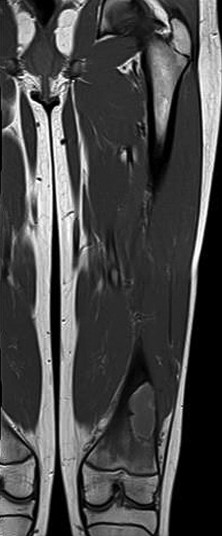

Question 37

An 18-month-old male is evaluated for congenital pseudarthrosis of the tibia (CPT). Examination reveals anterolateral bowing of the affected leg. Which genetic condition is most strongly associated with this finding?

Question 51

A newborn infant is noted to have severe anterolateral bowing of the right tibia. There are no fractures present on initial radiographs. The infant is at highest risk for developing congenital pseudarthrosis of the tibia (CPT). Which of the following genetic conditions is most strongly associated with this finding?